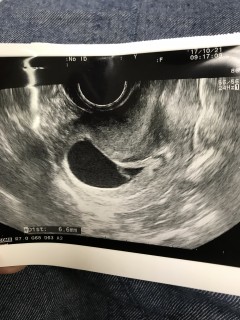

前回は胎芽も見えなくて出血もあったんですが今日心拍が確認出来ました。(*^^*) 上の子の時はつわりがなかったのですが若干つわりがでてきてもともとの低血圧とでほぼ横になってます。次回の検診が楽しみです。

前回の検診から2週間。 心拍確認ができるまで本当に長く感じました。楽しみにしてた検診の日、私はつわりらしき症状もなくドキドキしてましたが、エコーの映像でチカチカと点滅するのが見えて、前の検診よりも明らかに胎嚢の黒い影が大きくなってたのとその中に白い塊?みたいなのが見えて、これが赤ちゃんなんだなぁ~と、やっと実感できました☆8.6mmだそうです?今もつわりはなく、頻尿になったのと食の好みが変わったようか気がする程度ですが..これからも順調に育ってくれることを祈るのみです☆

7wちょうどの検診で赤ちゃんの心拍確認できました(*^^*)前回5w2dのときは胎嚢しか確認できず、今日の検診までの間とてつもなく長く感じました(^^;)つわりも全くないので余計に心配でしたが、先生の「このパタパタ動いてるのが赤ちゃんです」という言葉に一安心(^^)1cmくらいで大きさも相応だそう。まだ心配は続きますが、次回9wの検診で順調だったらリスクはぐっと下がるとのこと♪元気に育ってね(*^^*)